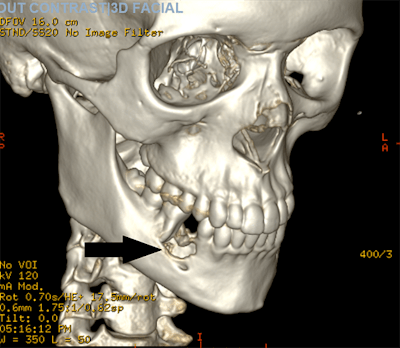

An oral surgery team was consulted, and a CT scan showed a lesion centered in the patient's right jaw with about 2.2 x 1.7 x 1.7 cm of erosion that went through the inner and outer cortex of the mandible. The erosion was centered on the roots of the right lower premolar teeth and first molar tooth with destruction of the second premolar tooth. This suggested a diagnosis of giant cell granuloma, and lab results from a biopsy sample confirmed it.